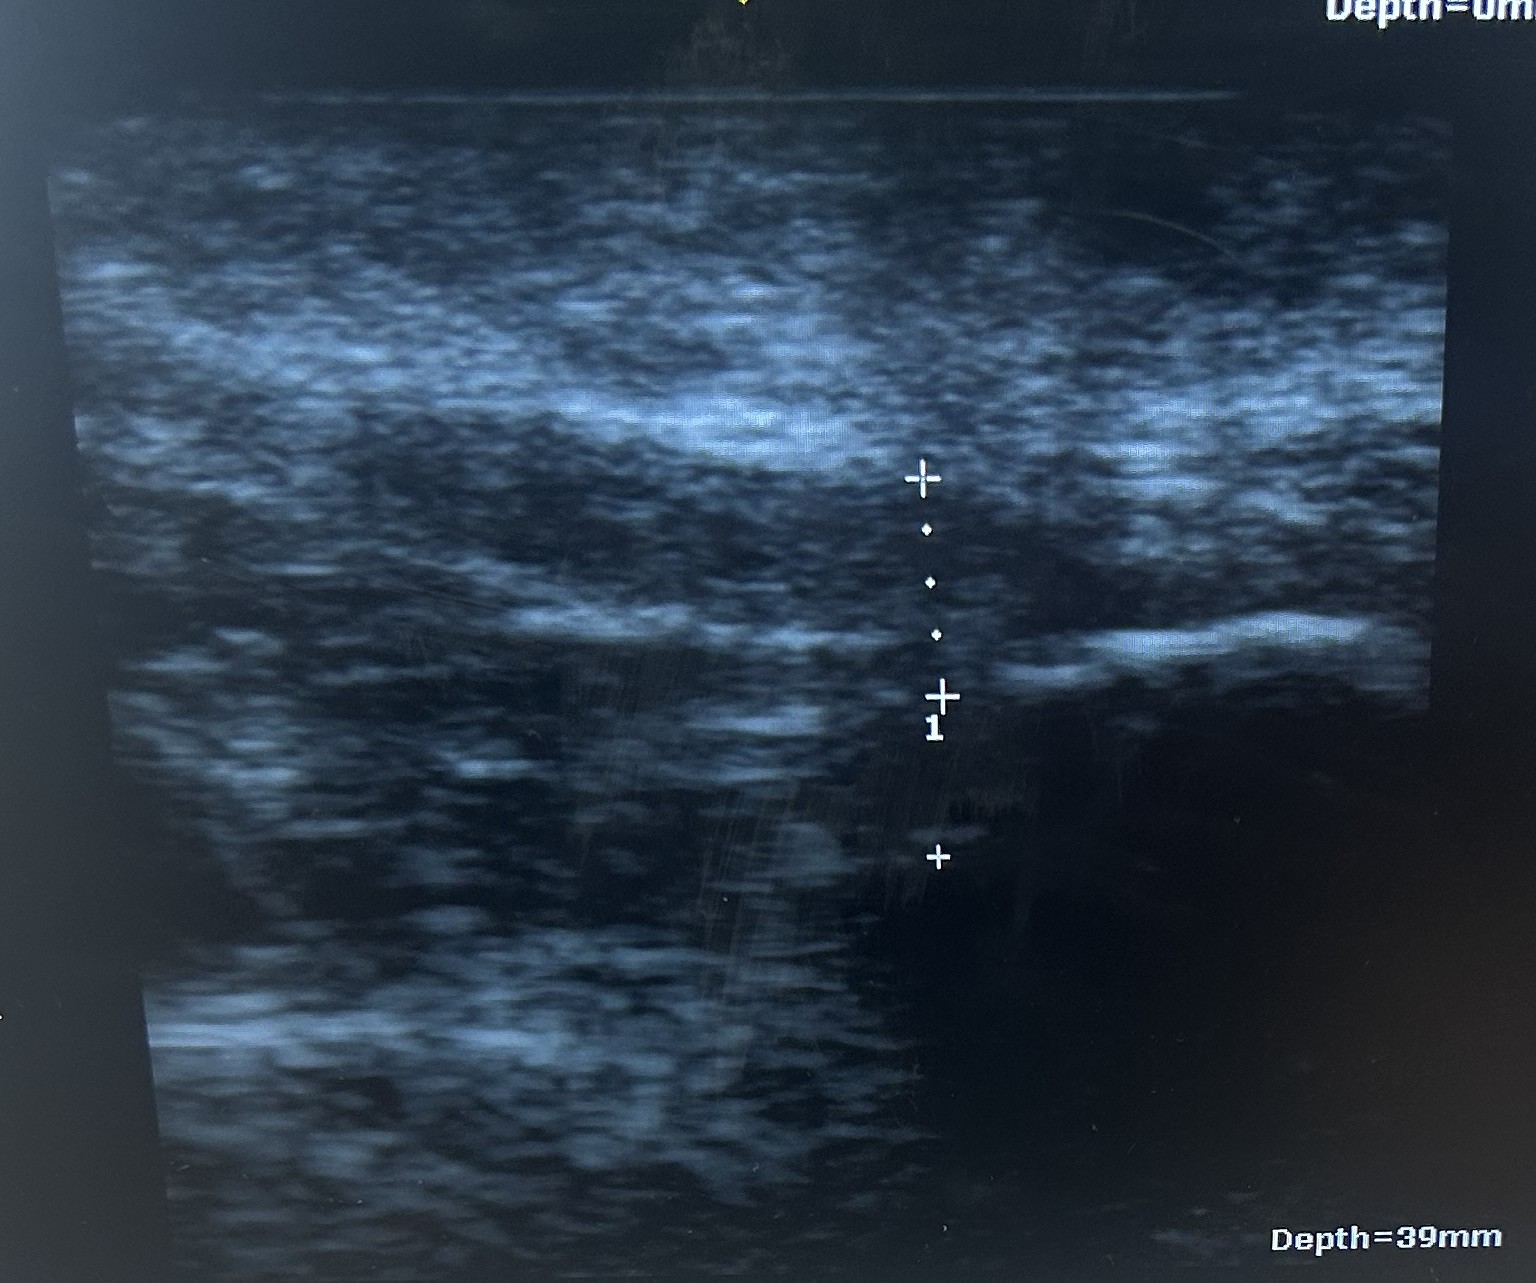

Heel pain could have many causes, like an injured bone or nerve, but the most common cause of heel pain is plantar fasciitis. This is one of the simplest diagnoses to treat due to similar pain patterns and a myriad of information online. The first step in the morning or after rest is the most common symptom, with severe sharp or dull pain in the base of the heel that may or may not get better with movement. The plantar fascia is a band of tissue the helps hold the arch up in walking, but over time, tight calves, unsupportive shoes, and minor trauma to the fascia causes heel pain. Plantar fasciitis can be diagnosed by exam, ultrasound, or MRI. Why is Dr. Barnett so adamant about proper education and treatment for heel pain? He is passionate about getting someone better as fast and affordably as possible, with no limitation to the treatments he recommends or uses. If someone knows why heel pain occurred, then they can resolve it and keep it from returning in the future.